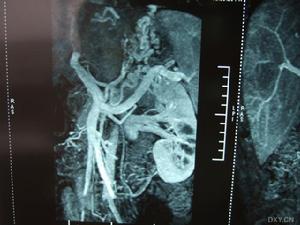

本CD-ROM為衛生部醫學CAI課件。本課件使用大量珍貴的臨床病例圖片、錄像、動畫和文字,配以解說,詳細介紹了布-加綜合徵(Budd-Chiarisyndrome)的臨床表現以及影像診斷,重點介紹其治療方法,主要包括適應證和禁忌證、介入治療器械、介入治療方法、最新進展、介入術後處理、併發症及處理。課件中附有練習題。課件內容豐富,資料寶貴,是學習布-加綜合徵的不可多得的輔助教材。本CAI課件由徐州醫學院製作,適用於醫學院師生以及臨床醫師學習使用。

病變累及肝靜脈或以上平面,則可有下腔靜脈高壓、門靜脈高壓(包括肝脾腫大、腹水、食管靜脈曲張和上消化道出血等)和心貯備功能不足(包括動則心悸、氣促)三組臨床表現。急性肝靜脈阻塞可因急劇進行性腹水、肝昏迷而死亡。